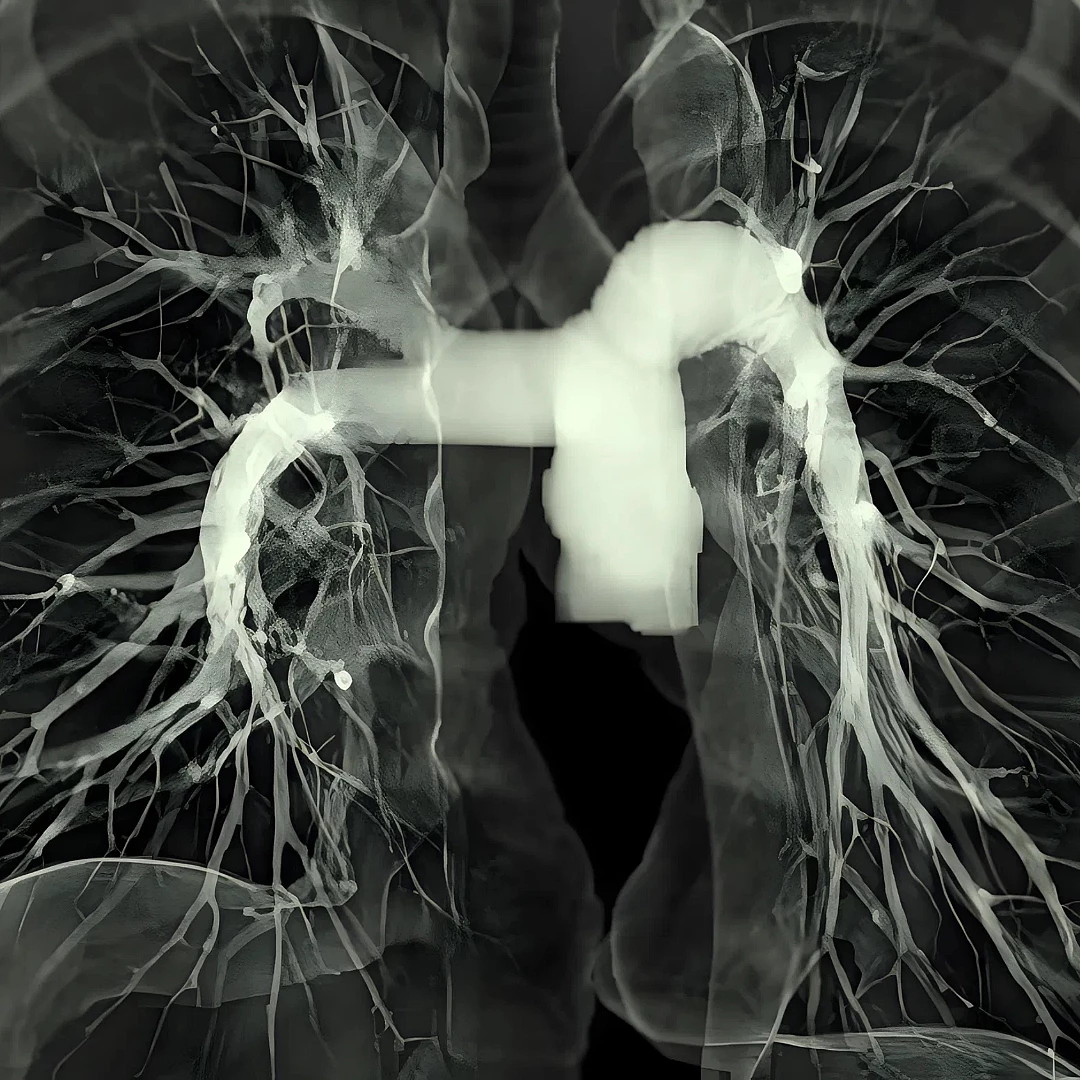

Standard & High-Resolution Chest CT

Standard and High-Resolution Chest CT provides detailed imaging of the lungs, airways, and chest structures to detect infections, tumors, or interstitial lung disease. High-resolution scans offer greater clarity for assessing subtle lung abnormalities with precision.

Pulmonary CT Angiography visualizes the pulmonary arteries to detect blood clots, such as in pulmonary embolism. It’s a fast, contrast-enhanced scan offering accurate diagnosis of lung vascular conditions.

Low-Dose Lung Cancer Screening CT is a quick, low-radiation scan designed to detect early-stage lung cancer in high-risk individuals. It enables early diagnosis, improving treatment outcomes and survival rates.

Virtual Bronchoscopy CT creates a 3D view of the airways using CT data, simulating a real bronchoscopy without inserting a scope. It’s a non-invasive method to detect airway abnormalities, tumors, or obstructions.